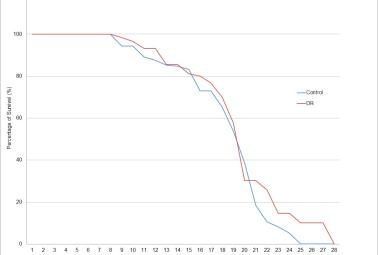

Parkinson’s disease (PD) is a neurological condition affecting the motor functions of the brain, characterised by the degeneration of dopaminergic neurons in the substantia nigra pars compacta region. The primary symptoms include dyskinesia, bradykinesia and resting tremors. This study investigated the potential impacts of Mitragyna speciosa or known as kratom on zebrafish with PD. 1-methyl-1,2,3,6-tetrahydropyridine (MPTP) solution was administered intraperitoneally to zebrafish to develop Parkinson’s symptoms in 2 to 3 days, followed by three concentrations treatment of kratom, for 28 days. On day 28, locomotor behaviour was evaluated to determine the duration spent in the top, middle, and bottom zones, total distance travelled and swimming speed. Then, the zebrafish were euthanised and preserved in a 10% formalin solution. Fixed zebrafish were processed and embedded in paraffin blocks for haematoxylin and eosin, and cresyl violet staining. The results of treatment groups showed that kratom had a neuroprotective impact, increasing time spent from bottom to top zone, distance travelled and swimming speed compared to the negative group. Moreover, the treatment groups experienced a rise in neuron regeneration and an enhancement in neuron appearance following a 28-day exposure to kratom. In conclusion, kratom shows promise as a potential treatment for PD by effectively reducing symptoms and improving movement.